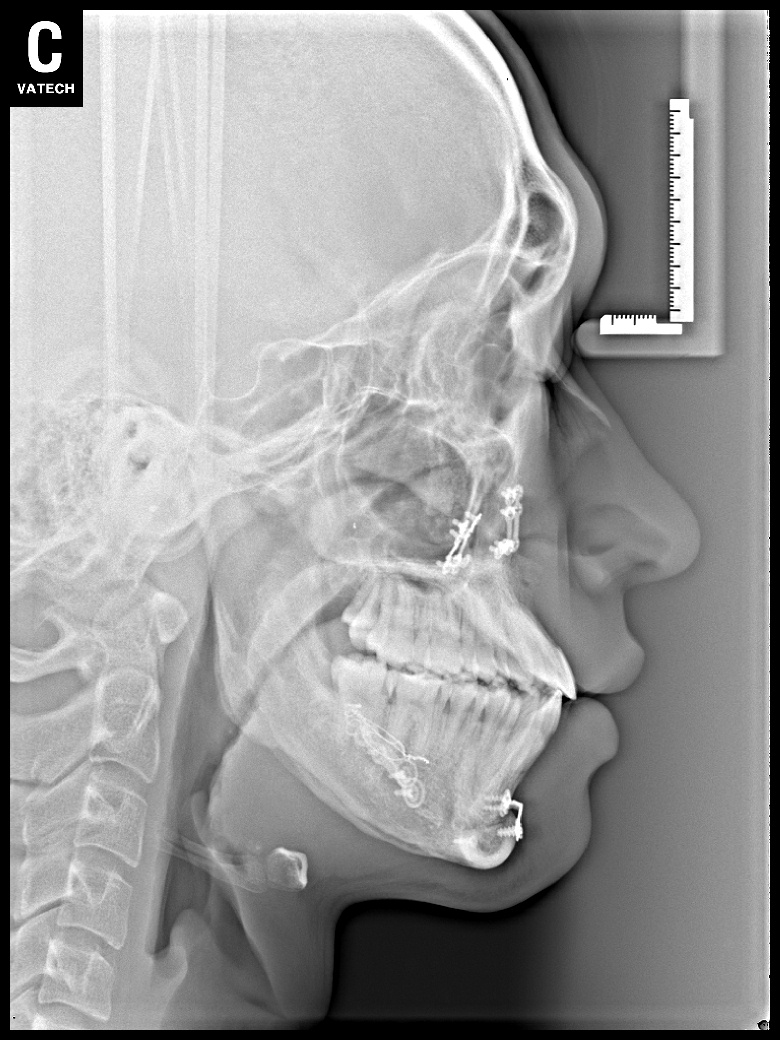

치료 후 사진입니다.